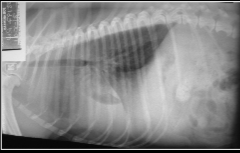

What is happening on this radiograph of a dog thats been involved in an RTA?

Haemothorax